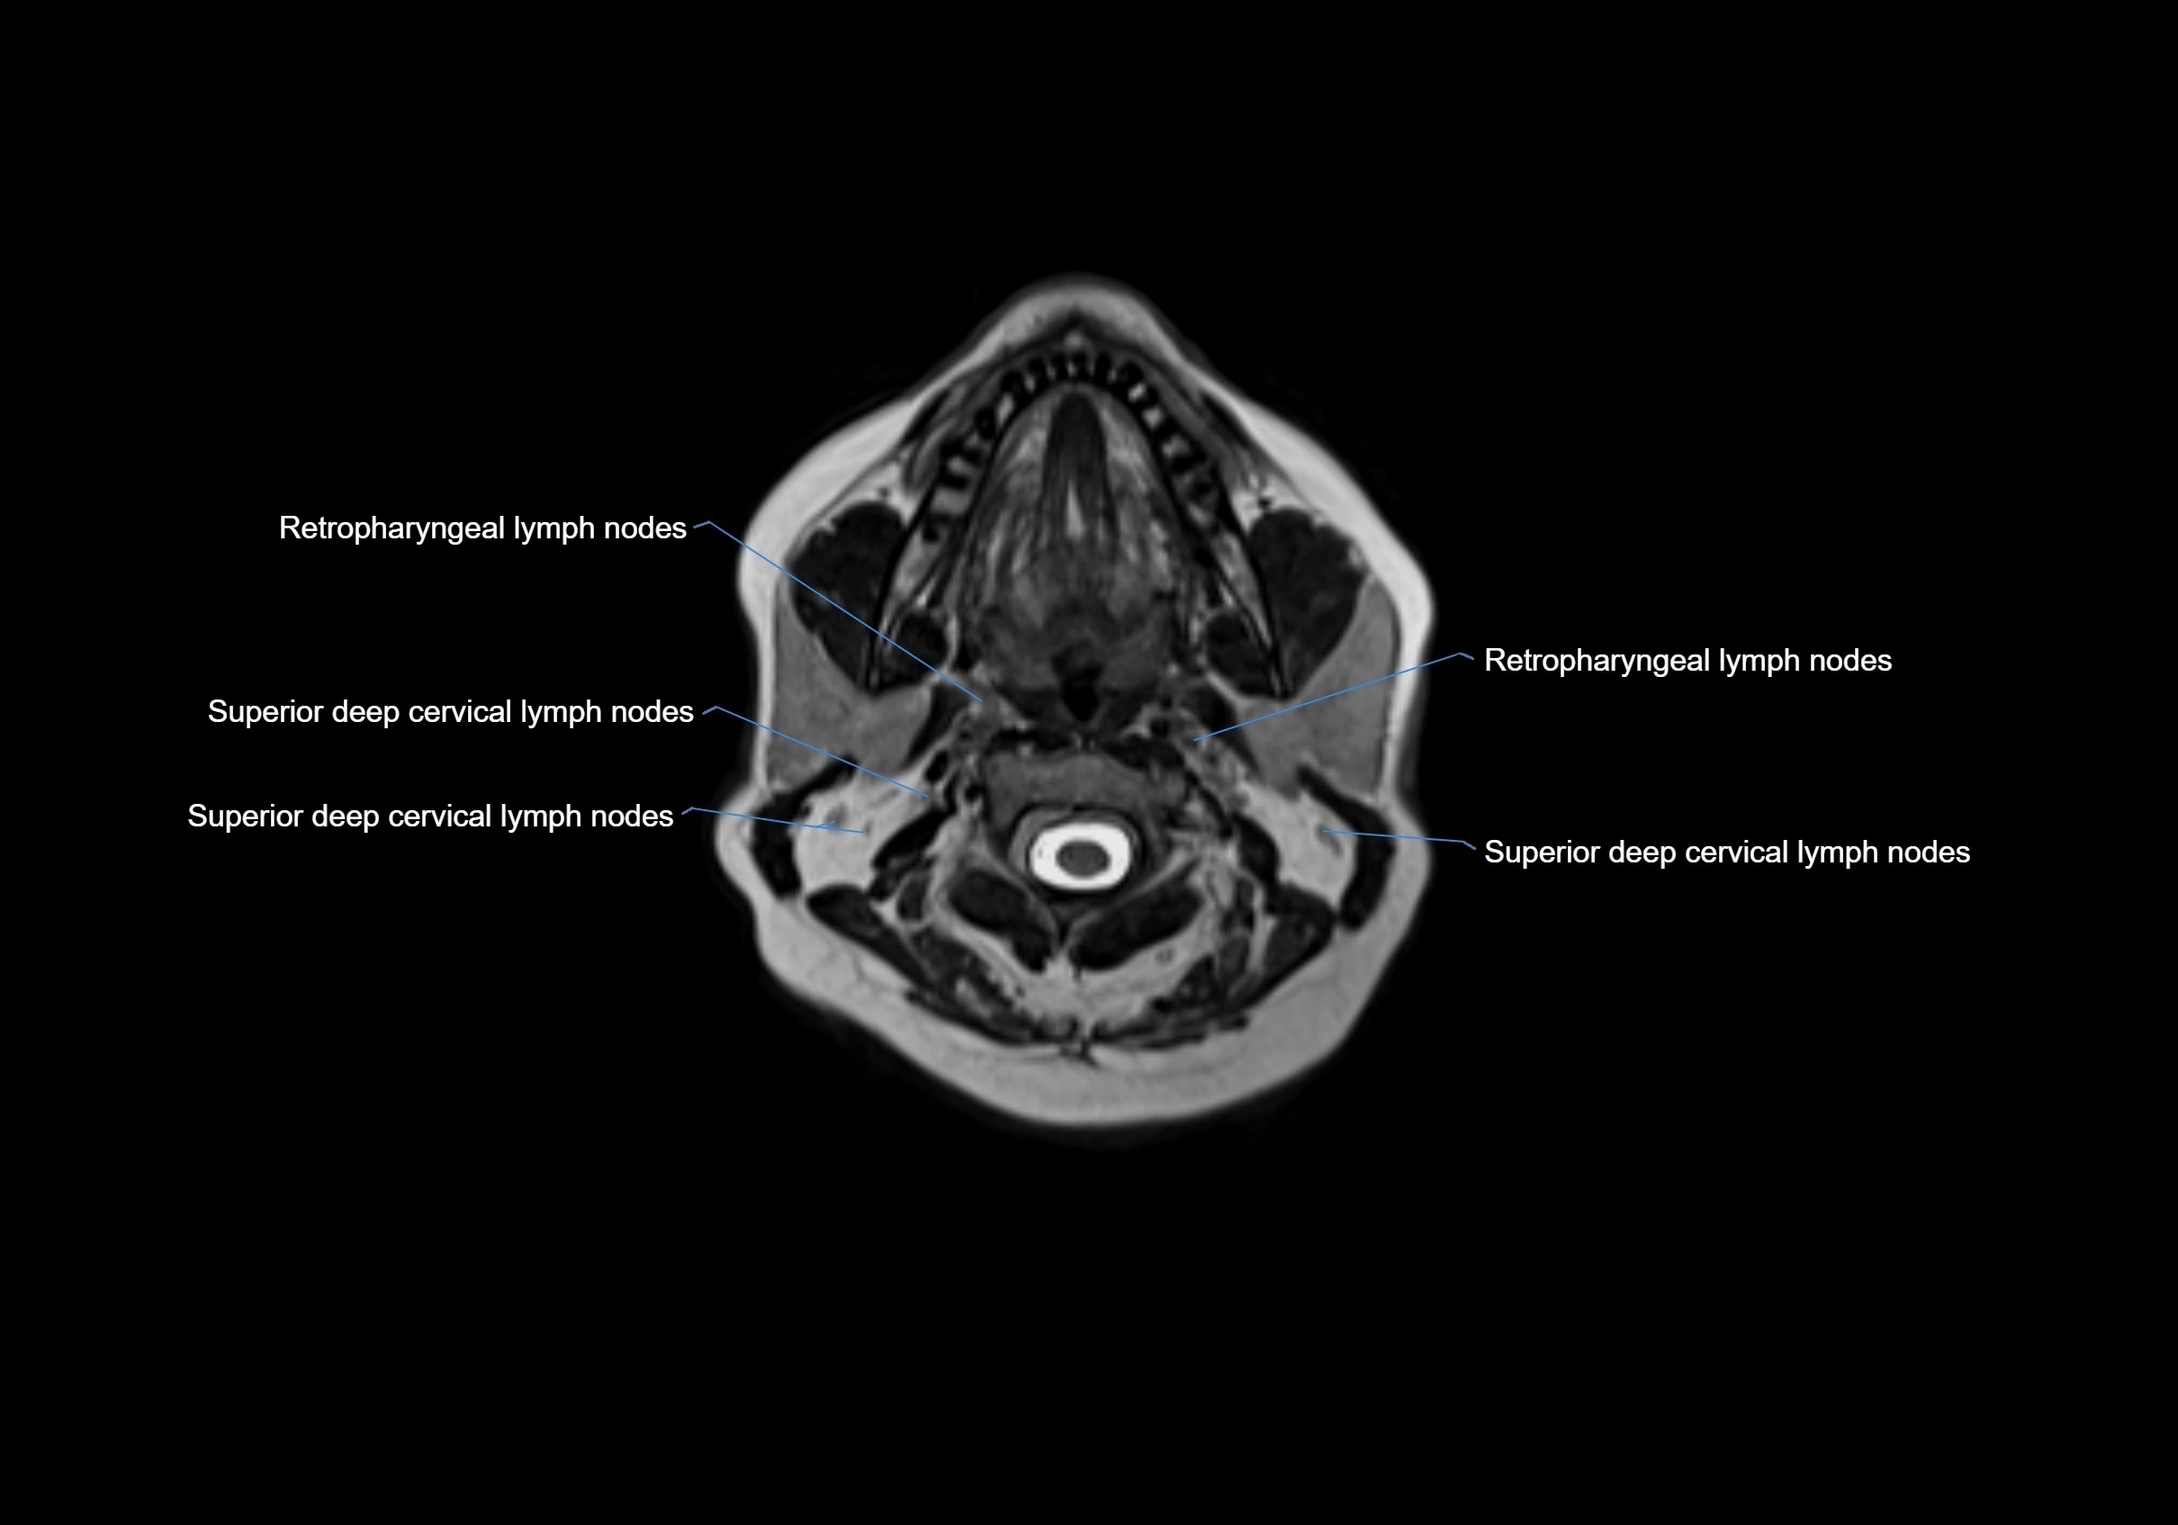

Location

• Found along primary lymph node chains, including preauricular, submandibular, parotid, and occipital regions

• Embedded in subcutaneous fat or superficial fascia, often lateral or posterior to primary nodes

• Variable in number; may occur unilaterally or bilaterally, depending on individual anatomy

MRI Appearance

T1-weighted images:

• Normal accessory nodes appear as small, oval hypointense to intermediate signal structures within subcutaneous fat

• Surrounded by hyperintense fat, enhancing contrast for visualization

T2-weighted images:

• Nodes show intermediate signal, with surrounding fat bright

• Useful for detecting edema, inflammation, or infiltration

MRI images

image